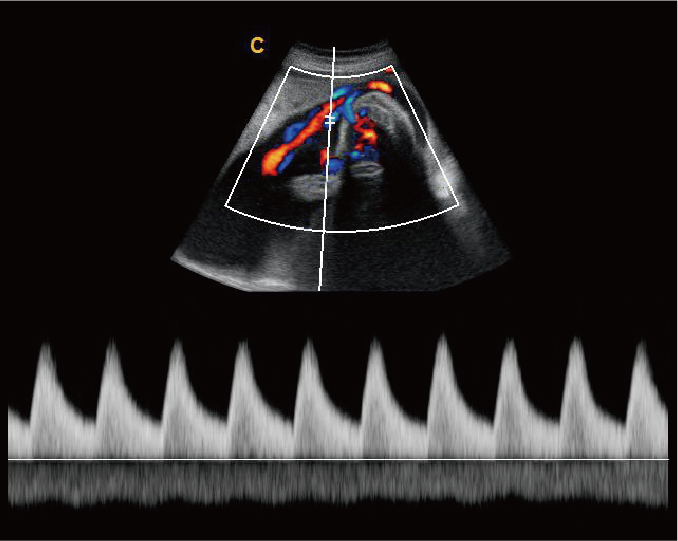

脐带血流频谱